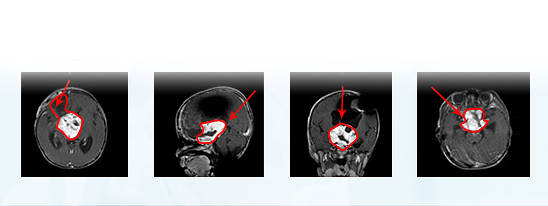

术前MR